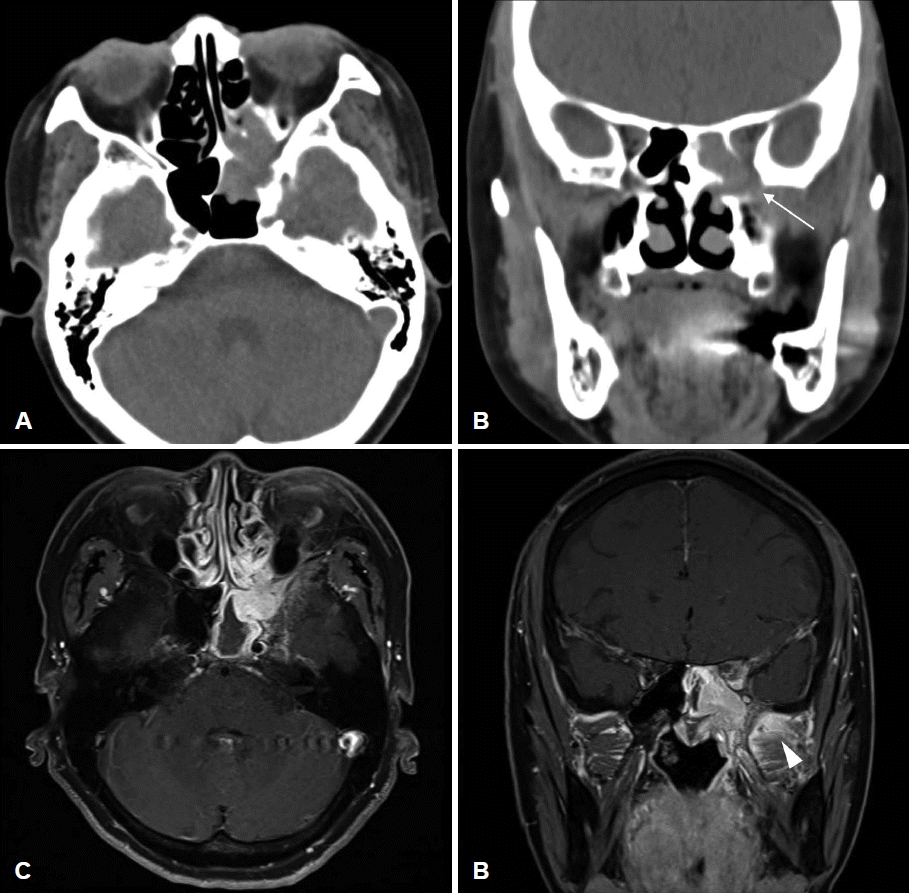

68세 여자 환자가 내원 3개월 전부터 시작된 좌측 안면부 통증 및 개구장애, 입술 감각 저하를 주소로 본원 신경과에 내원하였으며, 자기공명촬영에서 접형동의 종물 소견이 보여 이비인후과로 의뢰되었다. 과거력에서 고혈압, 고지혈증, 2형 당뇨, 불면증으로 경구 약제를 복용 중인 것 외에는 특이소견은 없었으며, 발열, 야간 발한은 호소하지 않았으나 최근 5개월간 63 kg에서 57 kg으로 6 kg의 체중 감소를 호소하였다. 비내시경검사에서 특이소견은 관찰되지 않았으며, 안과에서 시행한 시력검사, 시야검사, 안구운동검사에서 특이소견은 관찰되지 않았다. 부비동 컴퓨터 전산화단층촬영에서 좌측 접형동 및 후사골동의 연조직 음영이 관찰되었고 접형동 전외측벽의 골미란 및 골결손 소견이 보였다. 자기공명영상에서는 좌측 접형동 내에 T1, T2 강조영상에서 저신호를 보이고 gadolinium으로 균질하게 조영증가 되는 종양이 관찰되었다(Fig. 1).

Fig. 1.

A: Preoperative axial CT scan of the paranasal sinus shows soft tissue density opacity in the left sphenoid sinus and posterior ethmoid sinus. B: Coronal view shows bony erosion (arrow) of the anterolateral wall of the sphenoid sinus. C: Preoperative gadoliniumenhanced axial MRI shows a well-enhancing homogenous mass in the left sphenoid sinus. D: Coronal view shows increased enhancement at left masticator space (arrowhead), indicating tumor infiltration.